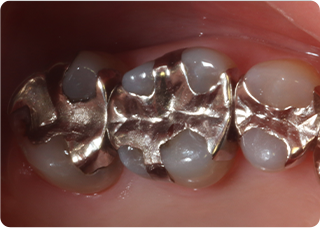

精密根管治療②

術前

術後

| 主訴 | 奥歯で噛むと痛い |

| 治療期間/回数 | 1ヵ月、3回 |

| 価格(税込) | 88,000円(税込) |

| リスク・副作用 | 病変再発、歯根破折の可能性 |

| ポイント | う蝕検知液を用い、むし歯の取り残しが無いようにし、ラバーダム防湿を行い、無菌的に根管治療を行った。根管充填材は、殺菌作用の強い保険適応外のMTAセメントを使用した。 |